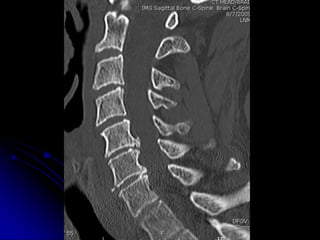

NON-CONTRAST

C-SPINE IMAGING

ALGORITHM

• CT

• MRI (depending upon Hx, PE, CT

findings)

• FLEX/EXT imaging (x-ray or CT

depending on CT/MRI findings and clinical

presentation)

1 2 3 4

WHICH PATIENT HAS ACUTE FX WITH SUBSEQUENT FUSION?

3

T6 T6

L2